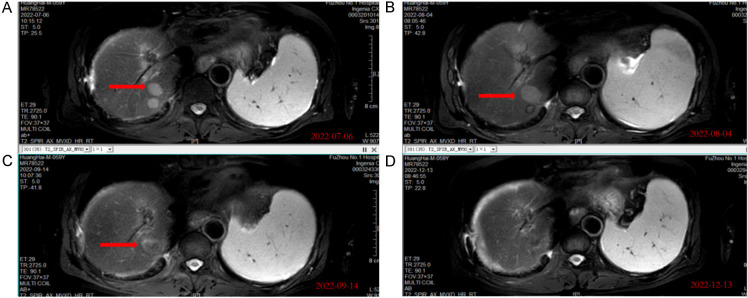

Figure 4.

MRI images of section VII liver showed tumor lesion shrinks gradually and vanished after 5 months. A. MRI images of section VII liver in baseline. B. Imaging results obtained after two weeks of the first administration of H101. C. Imaging results obtained after four weeks of the last administration of H101. D. Imaging results obtained after sixteen weeks of the last administration of H101 showed the lesion vanished.